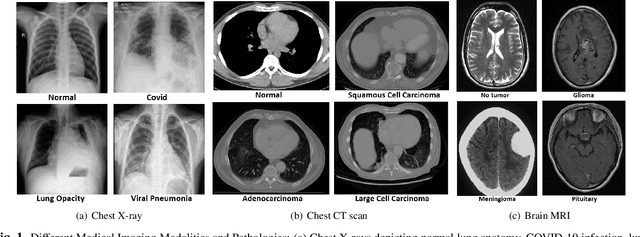

Abstract:Large Language Models (LLMs) are increasingly applied to medical imaging tasks, including image interpretation and synthetic image generation. However, these models often produce hallucinations, which are confident but incorrect outputs that can mislead clinical decisions. This study examines hallucinations in two directions: image to text, where LLMs generate reports from X-ray, CT, or MRI scans, and text to image, where models create medical images from clinical prompts. We analyze errors such as factual inconsistencies and anatomical inaccuracies, evaluating outputs using expert informed criteria across imaging modalities. Our findings reveal common patterns of hallucination in both interpretive and generative tasks, with implications for clinical reliability. We also discuss factors contributing to these failures, including model architecture and training data. By systematically studying both image understanding and generation, this work provides insights into improving the safety and trustworthiness of LLM driven medical imaging systems.

Abstract:This study presents a multimodal AI framework designed for precisely classifying medical diagnostic images. Utilizing publicly available datasets, the proposed system compares the strengths of convolutional neural networks (CNNs) and different large language models (LLMs). This in-depth comparative analysis highlights key differences in diagnostic performance, execution efficiency, and environmental impacts. Model evaluation was based on accuracy, F1-score, average execution time, average energy consumption, and estimated $CO_2$ emission. The findings indicate that although CNN-based models can outperform various multimodal techniques that incorporate both images and contextual information, applying additional filtering on top of LLMs can lead to substantial performance gains. These findings highlight the transformative potential of multimodal AI systems to enhance the reliability, efficiency, and scalability of medical diagnostics in clinical settings.